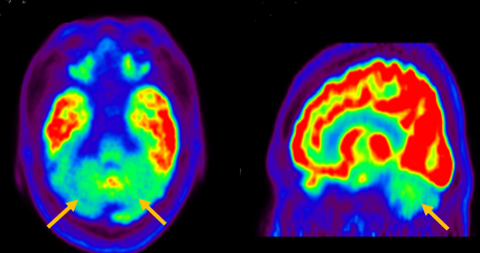

피질 기저핵 변성은 비대칭 증상을 두드러지게 보인다는 점에서 파킨슨병과 비슷합니다. 그러나 파킨슨병과 비교해 보았을 때 양측의 차이가 아주 심하게 나타난다는 특징이 있습니다. 질병 초기에 한쪽 손으로 동작을 하거나 계획된 행동을 하는 기능이 현저하게 떨어집니다. 간단한 손가락 모양도 따라 하지 못하는 현상을 보입니다. 또한 의지와 상관없이 제멋대로 움직이는 통제불능 손이 나타날 수 있습니다. 체위 떨림, 경축, 운동 완만과 같은 파킨슨병에서 볼 수 있는 증상들은 피질 기저핵 변성에서도 관찰될 수 있습니다. 또한 집중력 장애, 수행 장애, 이름 대기나 언어의 유창성이 떨어지는 등 전두엽 및 두정엽과 관련된 인지 장애가 나타납니다. 피질 기저핵 변성은 뇌 자기공명영상(MRI)에서 증상의 반대쪽 전두두정엽의 위축 소견이 특징적으로 나타납니다. 뇌포도당 양전자 단층촬영(PET)에서도 전두엽, 뇌기저핵에 비대칭적인 대사 저하의 소견이 보입니다.

[피질기저핵 변성 환자의 뇌포도당 양전자 단층촬영에서 확인되는 비대칭적인 대사 기능 저하]